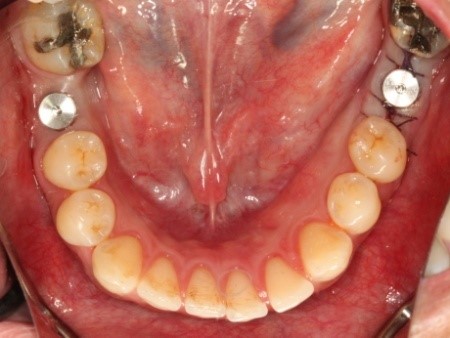

| Description | วัตถุประสงค์ของการวิจัยเพื่อศึกษาถึงความสำเร็จของการใช้รากเทียมในผู้ป่วยที่มีความวิการของกระดูกขากรรไกรที่จำเป็นต้องมีการปลูกกระดูกร่วมด้วย เพื่อศึกษาว่ารากเทียมและอุปกรณ์ที่ผลิตขึ้นสามารถใช้ได้ในทุกสภาพของกระดูกขากรรไกร โดยมีกระบวนการฝังรากเทียมในอาสาสมัครที่มีคุณสมบัติตามที่คณะผู้วิจัยกำหนดและติดตามผล ปัจจุบันอาสาสมัครได้รับการฝังรากเทียมและต่อครอบฟันครบแล้ว สามารถใช้งานได้ดี ประโยชน์ที่คาดว่าจะได้รับการศึกษานี้ ลดการนำเข้าของรากเทียม และสามารถต่อยอดเป็นการผลิตระดับอุตสาหกรรม |